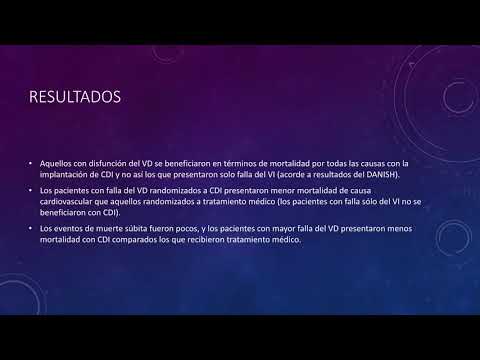

Disfunción ventricular derecha y el efecto de CDI en pacientes con insuficiencia cardíaca sistólica no isquémica. Dra. María Victoria Vannoni. Residencia de Cardiología. Hospital C. Argerich. Buenos Aires